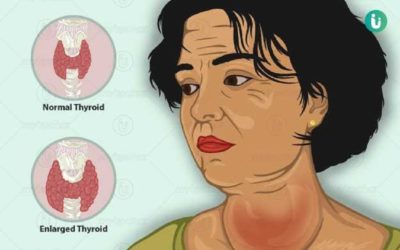

गलगाँड (थाइराइड)

गलगाँड के हो थाइराइड ग्रन्थिको आकार बढ्नुलाई गलगाड भनिन्छ । थाइराइड एक पुतलीको आकारको ग्रन्थि